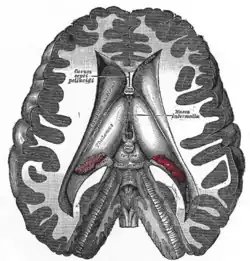

Przekrój poprzeczny mózgu pokazujący komory mózgu.

Każda z obu półkul mózgu zawiera w sobie jedną komorę boczną posiadającą łukowaty kształt, przypominający przechyloną nieco w dół literę „C”. W komorach bocznych wyróżnia się rogi przednie (cornu anterius ventriculi lateralis) sięgające do płatów czołowych, rogi dolne (cornu inferius) w płatach skroniowych, rogi tylne (cornu posterius) w płatach potylicznych oraz części środkowe. Komory boczne poprzez otwory międzykomorowe (foramina intraventricularia) łączą się z leżącą nieco niżej, ale położoną centralnie komorą III, znajdującą się częściowo w obrębie międzymózgowia. W tylnej części komory III rozpoczyna się wąski kanał – wodociąg mózgu, który nie zawiera splotu naczyniówkowego i przebiegając przez śródmózgowie łączy się z leżącą jeszcze niżej, również w linii środkowej, komorą IV. Ostatnia z komór znajduje się pomiędzy tylną częścią pnia mózgu a móżdżkiem. Komora IV posiada dwa otwory boczne (aperturae laterales ventriculi quarti) oraz jeden nieparzysty otwór pośrodkowy (apertura mediana ventriculi quarti), przez które płyn mózgowo-rdzeniowy przechodzi do przestrzeni podpajęczynówkowej.